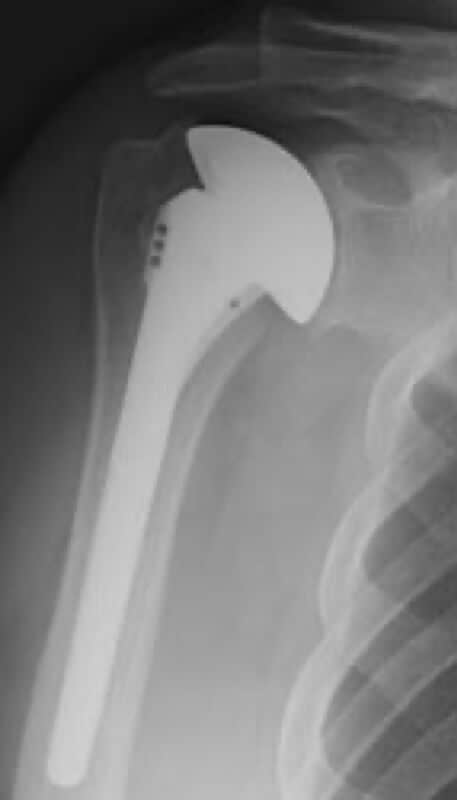

DePuy, Global Advantage